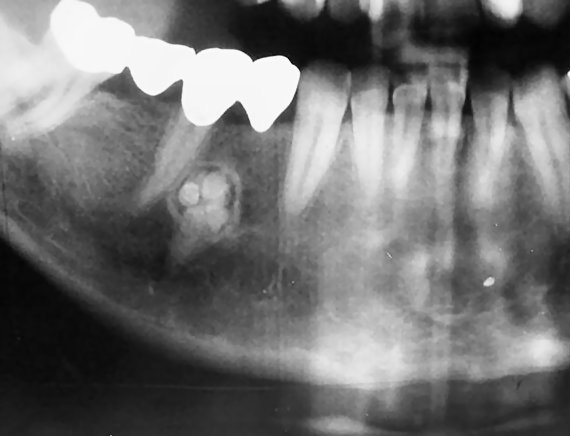

Одонтома нижней челюсти: фотографии и медицинская информация